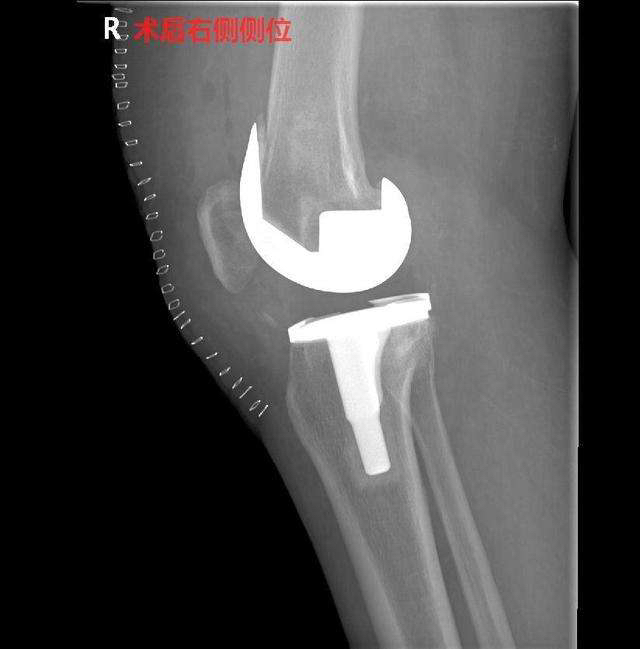

5、膝关节表面置换术,是膝关节的终极疗法,一般如果损伤加退变严重时再考虑终极疗法。